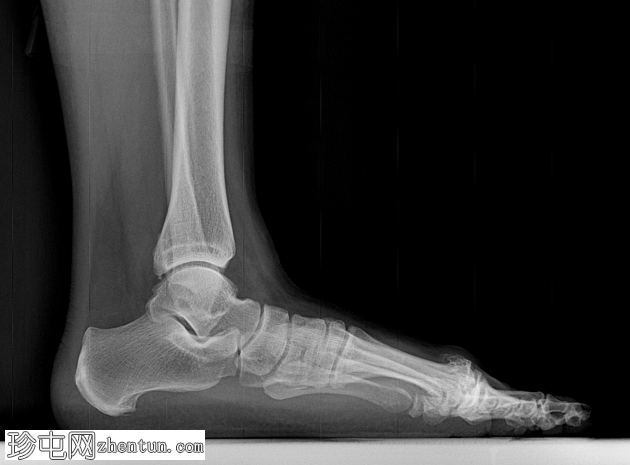

侧位

第一跖骨头背侧可见巨大骨赘。